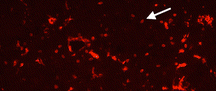

microglia.png